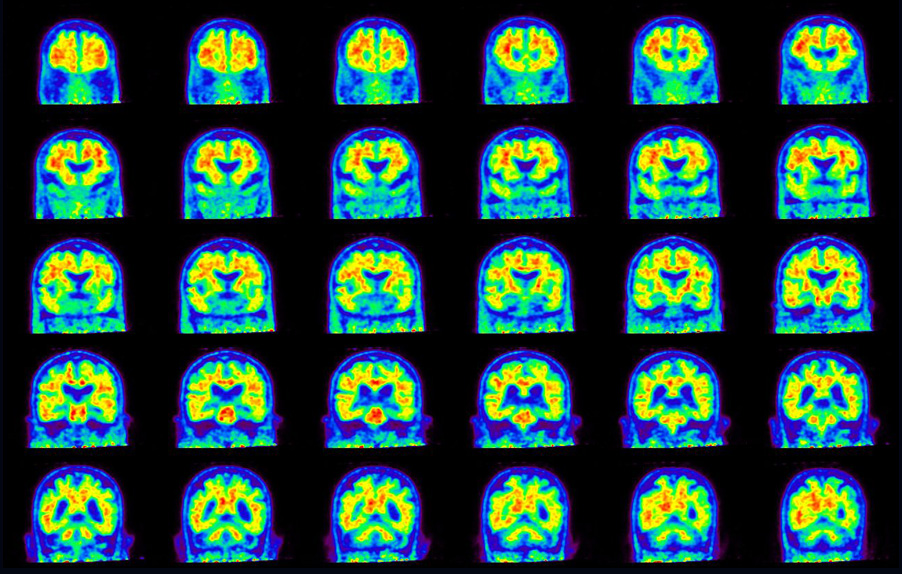

Coronal